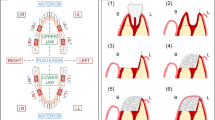

The defect created was usually refilled with new bone composed of a mixture of newly formed lamellar bone, with regions occupied by progressively maturing bone between them. Bovine particles (positive control group) revealed the fewest degradation signs. The granules were surrounded by mineralized tissue in direct contact, but some granules revealed poor bone growth directly connected to the periosteal region. In these cases, the bone ingrowth was replaced by highly vascularized, dense non-mineralized tissue (Fig. 2b).

In the test group, most of the particles were already degraded upon histological evaluation. This group presented a high regenerative potential, and only one case included a central area colonized by non-mineralized tissue. In the remaining cases (10 of 11), the defect was occupied by mineralized tissue with the same characteristics as the positive control group. The visible particles were completely surrounded by mineralized tissue (Fig. 2a).

The negative control group showed bone ingrowth inside the defect but with a partial collapse of the buccal bone inside it. This was not observed in the particle-treated groups (Fig. 2c).

Region of interest (ROI) includes the area of the defect surgically created, and was visible thanks to the type of staining used. Levai–Laczkó differentiates the pristine bone of the new or remodelled bone. ROI of the created defect was distinguished by the color change in the bone and the amount and percentage of biomaterial, bone, soft tissues and biomaterial plus bone together (Fig. 3). These were evaluated, considering the latter as the regeneration value. In a complementary manner, bone volume was studied relative to the total volume (BV/TV) and the percentage of bone to implant contact (BIC) and the contralateral bone. The descriptive data are summarized in Tables 1 and 2.